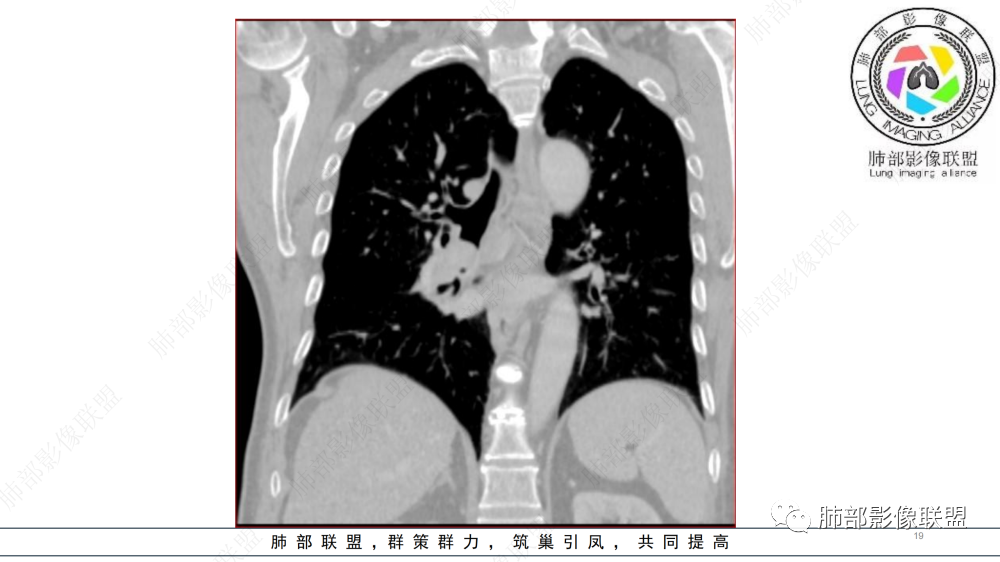

晨读 右肺中间段支气管至下叶支气管狹窄,腔内见软组织肿块,腔内外侵犯,右下肺门软组织肿块形成,不均匀强化,冠状位病变纵径大于横径,远侧肺内阻塞性炎症。定性恶性,考虑腺样囊腺癌或鳞癌

右肺下叶肺门区肿块,向中间段支气管突出,下叶支气管阻塞狭窄,腔内外侵犯,不均匀强化,内可见低密度,冠状位病变沿支气管走行生长,远侧肺内阻塞性炎症,考虑鳞癌,鉴别类癌

中老年男性,右肺下叶背段支气管内新生物,近端可见息肉样突起,远端沿分支支气管生长堵塞,肺门口病灶增强后明显强化,峰值达140hu,远端部分强化不明显考虑粘液栓,考虑典型类癌,鉴别鳞癌。

晨读:男,57,咳嗽半年,痰中带血3天。胸部CT:右中间段支气管到下叶支气管堵塞性狭窄,管腔内见软组织肿块,壁内外侵犯,长轴沿气道延展,下叶基底多段累及,病变纵径大于横径,远侧可见索条、阻塞性炎症。考虑恶性,腺样囊腺癌?鳞?鉴别N内分泌类、炎性肉芽肿等

气管截断,血管破坏,跨壁内外生长,阻塞性炎症,定性恶性,明显强化,首先考虑类癌,鉴别鳞癌